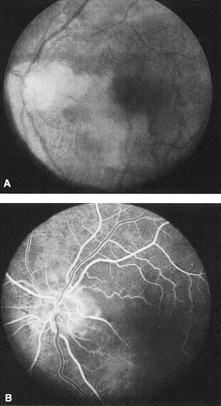

CENTRAL RETINAL ARTERY OBSTRUCTION Central retinal artery obstruction is one of the most sudden and dramatic events seen by ophthalmologists and was described as early as 1859.1 Although there have been numerous clinical and experimental studies of the pathophysiology of central retinal artery obstruction and although these studies have been augmented by the introduction of intravenous fluorescein angiography in the 1960s, the disease still has a relatively poor visual prognosis. The clinical picture is typically striking. Patients present with a sudden painless loss of vision. The appearance of a cherry-red spot in the fundus is characteristic (Fig. 1).2 The cherry-red spot appears because soon after obstruction of the blood flow to the inner retina, the normally transparent retina becomes opaque and blocks the brownish-red color from the underlying choroid, which is still supplied by blood. Because the retina overlying the foveola is relatively thin, however, the normal color of the choroid is still visible in this area.3,4 Although characteristic, the cherry-red spot is not pathognomonic for central retina artery obstruction.5 Sometimes the characteristic cherry-red spot does not develop; there may be only a slight accentuation of the brownish-red color in the foveola.4 It is not known how long it takes this cherry-red spot to appear, but in a primate model, it has appeared as early as 30 minutes after obstruction.6 An afferent pupil defect is usually present.2 With obstruction, virtually all eyes have narrowing and irregularity in the arteries and there is frequently an irregularity in the caliber of the retinal veins.2,4,6,7 Segmentation (boxcarring) of the blood column frequently develops; this segmentation is particularly noticeable in the veins and can be seen as a to-and-fro movement of the blood elements.3,4 Retinal hemorrhages, however, are not characteristic of central retinal artery obstruction.7 With time, the retinal opacity diminishes, generally leaving an optic nerve that is atrophic (Fig. 1). Frequently, thinned retinal arteries and veins also remain.7,8 No foveolar light reflex is evident, and a finely pigmented appearance of the macula is typical.7 In some cases, arterial collaterals develop at the optic disc.9–11 Rarely, anatomoses that exist between the central retinal artery and the ciliary arteries become visible as preretinal loops (Nettleship collaterals) after an occlusion at the edge of the disc.12,13,378In approximately 20% of patients, an embolus is evident somewhere in the arterial system.14 Emboli are discussed later. Intravenous fluorescein angiography is useful in showing the details of the abnormal circulation of a central retinal artery obstruction (Fig. 1). The principal abnormality is the delay in the appearance of the dye in the central retinal artery and its branches.2 Rather than the central retinal artery and its branches filling rapidly, considerable time may elapse before the entire arterial system is filled.15 The filling of the retinal arteries is often abnormal, with the fluorescein partially filling an artery (a dye front) or hugging the vessel wall, as in normal venous filling.15 Segmentation of the blood column is often well defined on fluorescein angiography.15 Venous filling is usually slowed and occasionally the dye does not progress beyond laminar flow during the study.14 In approximately 10% of eyes that have central retinal artery obstruction, there are abnormal choroidal filling defects, reflecting posterior circulation obstruction. These defects can occur even in patients who appear to have a typical central retinal artery obstruction.14 Leakage of dye from the vessel walls is not normally seen except at the site where an embolus lodges within a retinal artery.16 With time, the flow within the artery and its branches is reestablished and the appearance of the intravenous fluorescein angiogram may return to normal. The electroretinogram (ERG) is usually abnormal in central retinal artery obstruction. The b-wave is reduced, indicating a marked abnormality in the circulation of the inner retina.17,18 The a-wave, indicating normal photoreceptor function, is preserved or accentuated. There does not appear to be a good correlation, however, between the extent of b-wave abnormality and the degree of retinal function,3 although Yotsukura and Adachi-Usami420 reported that the b-wave amplitude increased with visual improvement. The photopic negative response (PhNR) shows severe depression in this condition reflecting the significant loss of the ganglion cells and their axons.377 The electrooculogram may be either normal or abnormal. Visual field defects are usually profound but either occasionally a small portion of the temporal peripheral visual field remains or the patient has a large central scotoma.3 The onset of obstruction occurs most often between the hours of midnight and 6 AM, with the second most common period being between 6 AM and noon.2 Most patients with central retinal artery obstruction complain of a sudden loss of visual acuity in the affected eye; most of these patients present with visual acuity ranging from finger-counting to light perception.14 Only about 5% of patients have visual acuity of no light perception and most of these have involvement of the posterior ciliary circulation, which can be seen on either intravenous fluorescein angiography or electrophysiology.14 Without a partial central retinal artery obstruction or a spared cilioretinal artery (to be discussed), it is unlikely that any patient will have initial visual acuity better than finger-counting.14 With or without treatment, most eyes retain visual acuity of finger-counting to light perception. Patients with a spared cilioretinal artery do not seem to have a follow-up visual acuity that is significantly different from those without a spared cilioretinal artery.14 Central retinal artery obstruction is caused by the disruption or cessation of blood flow to the central retinal artery, its branches, and the retinal layers supplied by those vessels. The inner two thirds of the retina derives its blood supply from the central retinal artery and its branches; the outer third of the retina is supplied from the choroidal circulation.19–21 The central retinal artery and its branches function as an end artery, and with the exception of a few anastomotic connections between the retina and the ciliary circulation at the optic disc, there are no other anastomoses.19 No intrinsic retinal vessels are present in the fovea because the inner retinal layers are not present in this area.19 Histopathologically, when a central retinal artery obstruction occurs, the retina initially becomes edematous. With time, all the retinal layers supplied by the central retinal artery and the artery's branches, including the nerve fiber layer, ganglion cells, inner plexiform layers, and the inner portion of the inner nuclear layer, are lost.20 In trypsin digest preparations after obstruction of the central retinal artery, the greatest change is in the capillary bed,22 where extensive ischemic changes take place. Usually, little attempt is made to repair the retina with gliosis or neovascularization.20 The most common site of obstruction of the central retinal artery is at the level of the lamina cribrosa.20 Clinically, it is possible to examine the blood flow velocity in the central retinal artery in a noninvasive manner, using a variety of techniques.21 The most useful appears to be color Doppler imaging, providing simultaneous Doppler and B-scan ultrasound images of the optic nerve head, which primarily represents flow in the central retinal artery.23 Studies using this technique demonstrate a marked reduction of or no blood flow in the central retinal artery with an acute central retinal artery occlusion that returns to normal with time.24 Characteristics of the retinal blood flow can be measured clinically with retinal Doppler velocimetry.385 This is an instrument that can measure the blood column diameter, the centerline blood velocity, and the blood flow in major retinal vessels. However, when evaluating the blood flow in the optic nerve, choroidal, and retina, the Doppler laser flowmetry is more sensitive to the blood flow in the superficial layers than in the deeper layers.410 Masaoka and colleagues384 studied the hemodynamic changes in the retinal circulation with a scanning laser ophthalmoscope and intravenous fluorescein angiography. This technique allows the assessment of erythrocyte velocities and movement with high resolution continuous images and is a useful technique for the evaluation of hemodynamic changes in vascular occlusions. Analysis of the retinal nerve fiber layer by one of the confocal laser scanning tomography techniques can provide information about a central retinal artery occlusion. Foroozan and co-workers383 studied patients with a central retinal artery occlusion within 1 week of occlusion with a scanning laser polarimeter. Diffuse attenuation of the retardation of the nerve fiber layer surrounding the optic nerve was seen in all eyes studied. Four patients were scanned in follow-up at intervals ranging from 1 week to 6 weeks; all had unchanged studies.383 Optic coherence tomography (OCT) of an acute central retinal artery occlusion shows a slight increase in the thickening of the retina and reflectivity of the inner layers of the retina that correspond to the opacity seen clinically (Fig. 1).409 With time, the disc becomes atrophic and the retina thinner. Experimental studies of central retinal artery obstruction in the cat25 and the rhesus monkey26–28 have increased our understanding of arterial obstruction. The most clinically relevant finding is that there is a period in which a total lack of blood flow (ischemia) to the inner retina can be tolerated; that is, if the blood flow is not obstructed longer than this period, visual function may return to normal. This critical time in the cat eye is 90 minutes,25 and in the young, healthy rhesus monkey it is 100 minutes26–28—any longer than this and the histologic changes are irreversible and the animal has permanent visual loss. Hayreh and co-workers379,380 have repeated this experiment to determine how long the retina can survive central retinal artery occlusion in middle-aged and elderly rhesus monkeys, a situation that might be more applicable to the human situation where most occlusions occur in older patients. That study showed that an occlusion of less than approximately 100 minutes produced no permanent damage and that an occlusion of longer than 240 minutes produced massive and irreversible retinal damage. It is not known why the older monkeys had a longer retinal survival time with occlusion of the central retinal artery than younger monkeys. Because there is no evidence that the monkey and the human have different retinas,379 the studies by Hayreh and co-workers have implications for studies that attempt to treat central retinal artery occlusion. Any treatment of this condition will almost certainly have to be initiated within 100 to 240 minutes, assuming the occlusion is total, or the patient will likely have permanent damage to the retina, regardless of treatment. On average, central retinal artery obstruction occurs in patients who are in the fifth or sixth decades of life, with the age range varying from 17 to 84 years. Fewer than 10% of patients are younger than 30 years of age.14,29,30 In some cases, the cause of central retinal artery obstruction is relatively clear, such as when due to a visible embolus. In other cases, however, especially when found in association with a systemic disorder such as diabetes, the association is less clear. Table 1 lists some of the conditions associated with central retinal artery occlusion. Arteriosclerosis is probably the most commonly associated systemic condition. With the progressive buildup of subendothelial atheromatous material, the lumen of the central retinal artery becomes narrowed over time and eventually may become occluded.20 This association is inferred because most patients with central retinal artery obstruction are in the fifth to sixth decades of life, when atherosclerotic changes are expected. TABLE 1. Conditions Associated With Retinal Arterial Obstructions